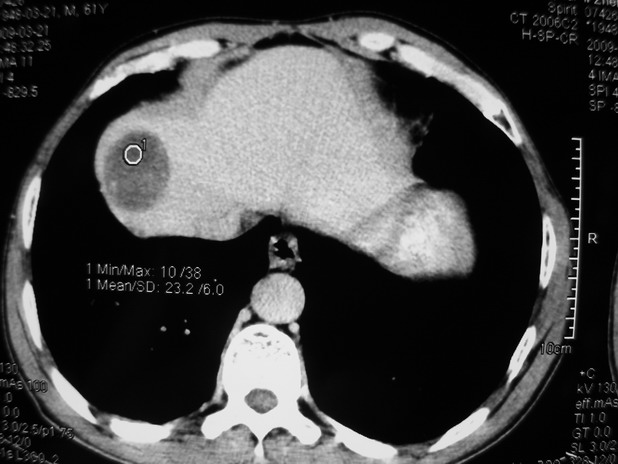

以下是引用余辉在2009-3-21 21:36:00的发言:[br]图像太乱了,建议楼主直接将强化数据按顺序列出来,病灶位置较表浅薄,有肝炎病史,灶内实性成分有显著强化,动脉期约60hu,考虑肝癌可能性大,进一步检查。